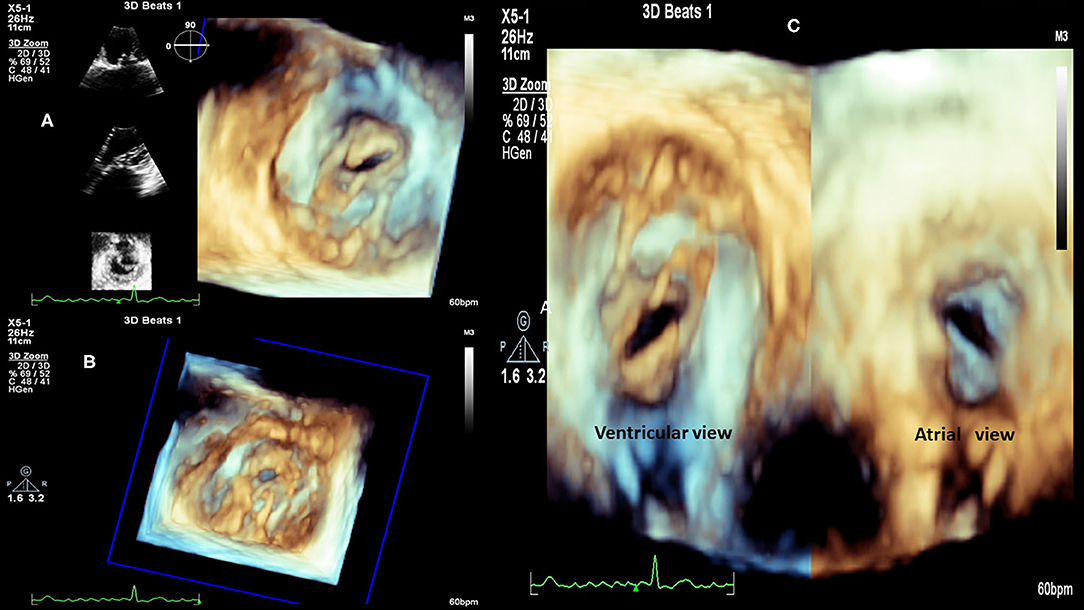

FIGURE 2

www.frontiersin.org

Figure 2. RHD (Mitral valve stenosis). (A) 3D transthoracic echocardiography, left atrium view, 2D reference structures, patient with severe valve mitral stenosis. (B) 3D transthoracic echocardiography, patient with severe valve mitral stenosis. (C) 3D transthoracic echocardiography, view from left atrium (right) and from the left ventricle (left), patient with severe valve mitral stenosis.